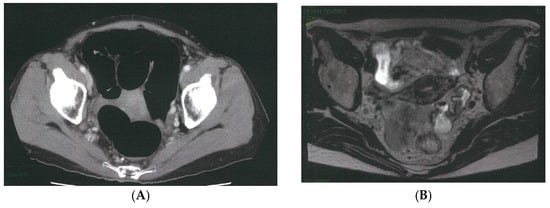

The caudal and dorsal extents of dissection are confirmed by identifying key anatomic landmarks, including the coccygeus muscle, the tendinous arch of the levator ani, the levator ani muscle itself, and the internal pudendal artery as it enters the Alcock canal. The distal margin of the 263D field is then connected seamlessly with the caudal aspect of the obturator compartment (station 283), allowing residual nodal tissue to be mobilized from the inferior vesical vessels and ensuring complete clearance of the distal internal iliac basin. Figure 3 illustrates a representative case of metastasis to the distal internal iliac lymph node (station 263D), the most commonly involved lateral pelvic site in advanced lower rectal cancer.

Figure 3.

Representative case of metastasis to the distal internal iliac lymph node (station 263D), the most common site of lateral pelvic involvement in advanced lower rectal cancer. (A) Pelvic CT demonstrates a clearly enlarged lymph node along the Alcock canal (arrow). (B) Pelvic MRI confirms a suspicious node located inferior to the superior vesical artery and adjacent to the inferior vesical vessels (arrow). (C) Intraoperative robotic view of the left lateral pelvic compartment showing a prominently swollen station 263D node (dotted circle). (D) Post-dissection view following complete excision of the station 263D lymphatic basin, including removal of the enlarged node, which was subsequently confirmed as metastatic on pathological examination.